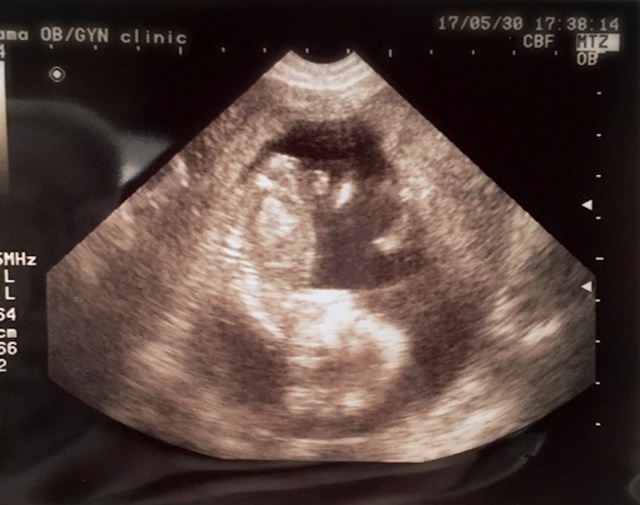

12週0日(12w0d・女の子)|yuki0255 さん(23歳)

エコー写真撮影時のエピソード:

初めの頃は、カシューナッツみたいで人間らしさもなかったのに、それでもそれがまたかわいくて次の検診が楽しみで毎日を過ごしていて、やっと人間らしくなって前よりも愛おしく思えました。

今でも寝る時は横を向いて寝るので、お腹の中と同じポーズだなぁと思いながら我が子を眺めてます。